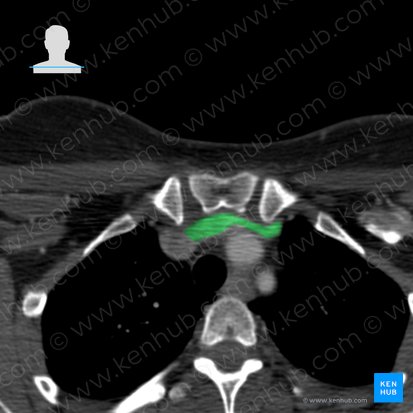

Die Vv. brachiocephalicae dextra und sinistra entstehen jeweils aus der Vereinigung der gleichseitigen V. jugularis interna mit der V. subclavia im Angulus venosus (Venenwinkel) hinter dem Sternoclaviculargelenk. Sie liegen gänzlich im oberen Mediastinum.

Die deutlich längere V. brachiocephalica sinistra zieht von ihrem Entstehungspunkt über den Aortenbogen und hinter dem Manubrium sterni schräg abwärts. In ihrem Verlauf kreuzt sie die Aa. thoracica interna sinistra, subclavia und carotis communis sinistra, die Nn. phrenicus und vagus dexter sowie den Truncus brachiocephalicus und die Trachea.

Aus dem Zusammenfluss beider Gefäße entsteht retrosternal auf Höhe des 1. Rippenknorpels die Vena cava superior. Der Längenunterschied der beiden Vv. brachiocephalicae ist durch die asymmetrische Lage der V. cava superior rechts der Aorta bedingt.